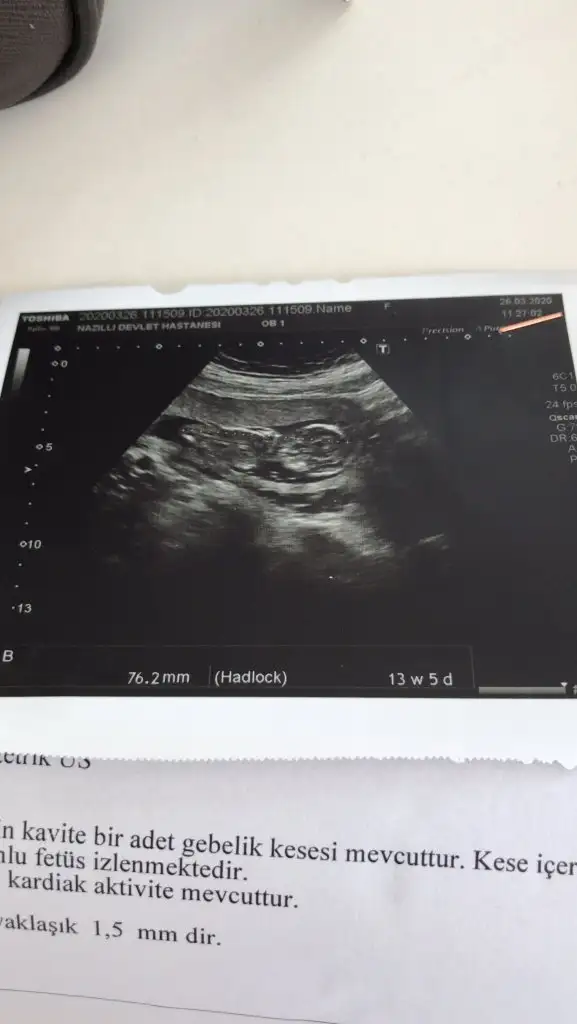

Nubu ne dik nede paralel 11 yada 12 hafta usg varsa paylaşın emin olamadım çünki nubu tam karşıya bakıyorMerhaba 13+2 deyim. Cinsiyetini öğrenemedim. Yorumlarsanız sevinirim.

Kız gibi geldi emin olamadım 13 haftayıda paylaşınusg 12 hafta ile uyumlu bana da bakar mısın rica etsem canm

Bugün kü usg bu canm son gittiğim yani buKız gibi geldi emin olamadım 13 haftayıda paylaşın